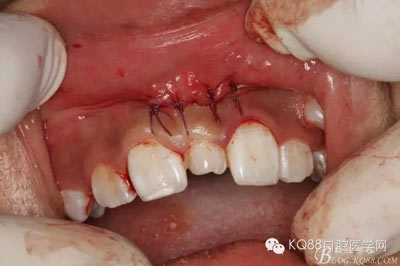

圖17.縫合四針,患者鼻腔正常,無出血。切口小,手術簡單明了,創(chuàng)傷小。

圖18.然后拔除萌出的多生牙,這樣做,可以防止先拔萌出多生牙導致出血多,影像拔埋伏多生牙的手術視野

圖19. 萌出多生牙創(chuàng)口也縫合兩針,手術結束。